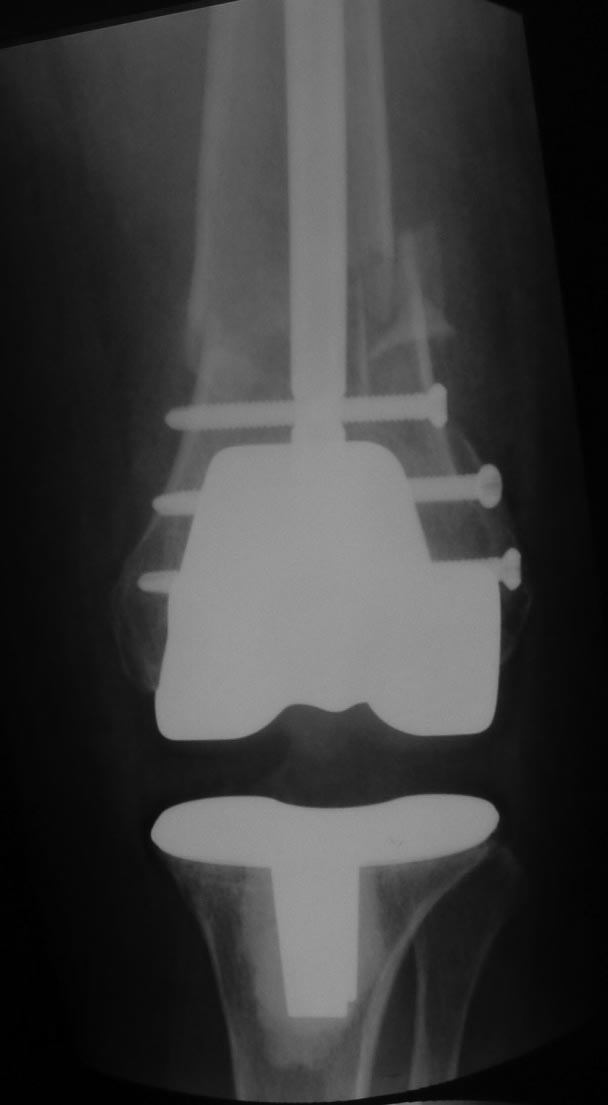

Вот обещанный в чем-то похожий случай. Пациентка 58 лет с тяжелым ревматоидным артритом. Оперировал в 2013 г. В одну сессию сделал чрескожно повторную операцию на стопе (раньше где-то оперировали, пациентка приехала издалека) и малоинвазивный артродез голеностопного сустава (имелась варусная деформация, как компенсация вальгуса колена, на фоне выраженной ревматоидной артропатии). А через неделю – протезирование коленного сустава (фиброзный анкилоз после когда-то выполненной синовэктомии, грубая вальгусная деформация). Понятно, что неделю между операциями стопа торчала в сторону и не была опороспособной. Основное пожелание по коленке было, чтобы сгибалась хоть немного для походов в театр. В конечном счете, сустав сгибался до 90 гр. Фотография стоя была прислана через 2 года после операций. А через 3 года, прошедшим летом, пациентка упала с лестницы: перипротезный перелом бедра. Через 5 дней приехала оперироваться. Отсюда отек на фото стопы. Что интересно, через 2 мес. после остеосинтеза пациентка написала, что только теперь, после перелома, смогла ощутить опору всей поверхностью стопы. До этого пользовалась индивидуальными стельками.